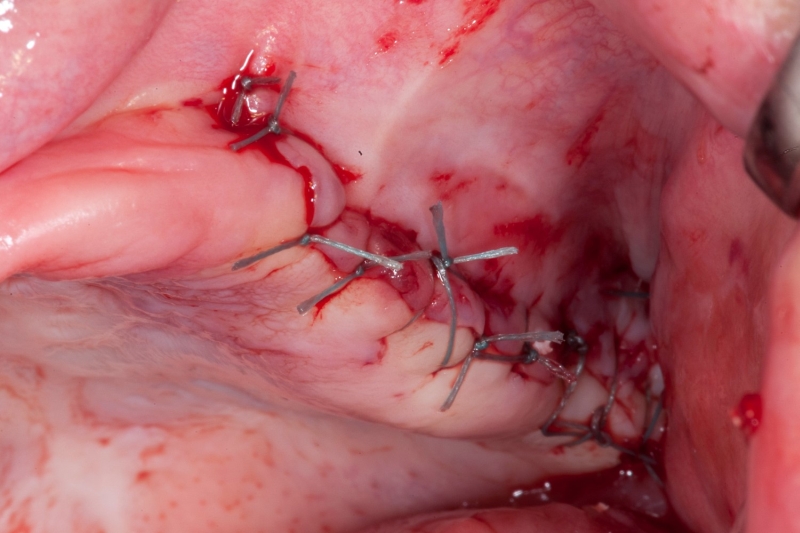

17/18 - Tension-free suturing after placement of Jason® membrane

Vertical augmentation & sinus lift with maxgraft® bonering - Dr. O. Yüksel and Dr. B. Giesenhagen